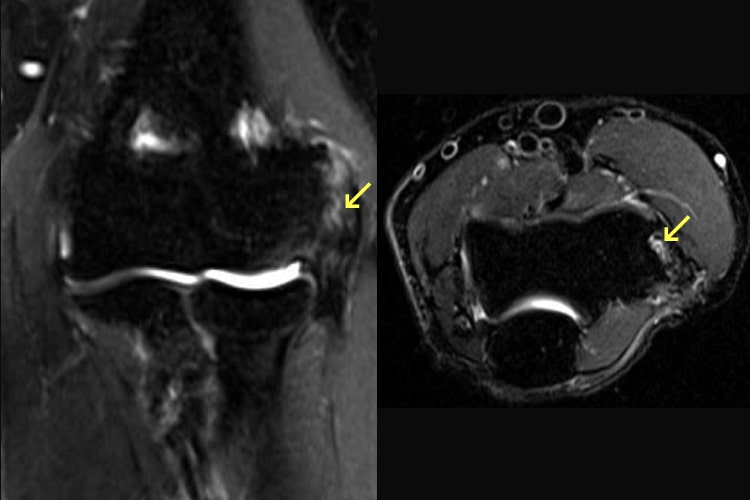

外側型の離断性骨軟骨炎写真1 外側型の離断性骨軟骨炎写真2

外側型の離断性骨軟骨炎

野球肘には内側型と外側型があります。内側型は軟骨が靭帯に引っ張られることにより痛みが発生し、多くは数週間の投球中止と正しいフォームを身に付けることで治ります。一方、外側型は離断性骨軟骨炎と呼ばれ、投げ方や投球数に限らず発生します。初期であれば保存的な治療で障害を残さず治りますが、進行すると手術が必要になったり、肘の動きが制限されて野球を続けることが難しくなります。